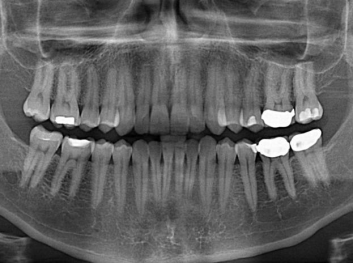

損壞的牙齒如何自我修復(fù)?近日,來自哈佛大學(xué)和諾丁漢大學(xué)的研究人員研發(fā)了能夠刺激牙齒干細(xì)胞再生的新型生物材料,而這種新材料研發(fā)成功的背后,正源于他們對牙齒如何實現(xiàn)自我修復(fù)這個課題的不斷探索。

據(jù)美國期刊《大眾科學(xué)(Popular Science)》報道,此種新型生物材料,不僅可以有效地取代傳統(tǒng)補牙填充物,刺激牙齒干細(xì)胞再生,患者也有望無需再接受根管治療,使蛀牙患者免除牙根感染或牙髓壞死的苦惱,一個全新的牙齒治療時代即將來臨。

Adam Celiz,是來自諾丁漢大學(xué)的研究人員,他和同事開發(fā)的這種新型合成生物材料,能刺激干細(xì)胞在牙髓部的生長。與普通材料一樣,這種合成材料被填充到牙齒并用UV光硬化。

在體外測試中,材料刺激干細(xì)胞進入牙本質(zhì)的增殖和分化速度,促進形成牙齒骨組織。研究人員認(rèn)為,一旦材料在受損牙齒中應(yīng)用,這些干細(xì)胞可以自動修復(fù)來自填充物上的損壞。在本質(zhì)上,該生物材料將使牙齒自愈。